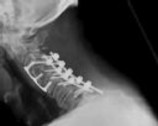

Figures 1 and 2 are CT scans obtained from a 68-year-old man who has had

progressive neck pain and stiffness, worsening gait imbalance, upper extremity weakness, early muscle fatigue, difficulty with fine motor control, and difficulty with activities of daily living over the past few years. On physical examination, he has a wide based stiff legged gait, generalized upper extremity weakness, dense sensory loss in the upper and lower extremities, and markedly brisk reflexes. What is the most appropriate treatment for this patient?

4. Posterior cervical laminoplasties from C3-6 Discussions: D

This patient has progressive myelopathy secondary to ossification of the posterior longitudinal ligament. Diagnostic imaging reveals multilevel cervical cord compression from C4-6. The patient has maintained reasonable cervical lordosis. A posterior procedure such as multilevel laminoplasty

decompresses the spine, is motion preserving, and has a low complication rate. Observation and cervical epidural injections are not viable options in patients with progressive myelopathy. Anterior cervical decompression, including corpectomy, is an option; however, anterior procedures have an increased risk of complications such as dural tear or cerebrospinal fluid leak. The axial CT image shows a "double layer" sign, which is consistent with dural ossification and increases the risk of dural injury with anterior decompression